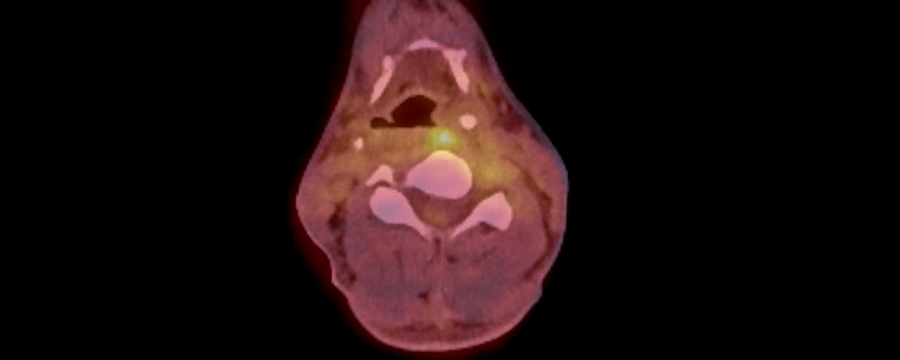

El PET-TAC es una técnica que consiste en combinar la tomografía por emisión de positrones con la tomografía axial computarizada. De esta manera, se obtienen imágenes muy bien detalladas de los tejidos y órganos del cuerpo que se necesiten observar y analizar para poder establecer un diagnóstico acertado y más rápido.

La tomografía por emisión de positrones produce imágenes tridimensionales que permiten observar cómo funcionan los tejidos y órganos del cuerpo. Al contrario que la tomografía axial computarizada no utiliza rayos X, sino un fármaco que se inyecta en el paciente y que se va a acumular en aquellas áreas donde la actividad metabólica es mayor, permitiendo observarlas con claridad. Aunque, para que los resultados sean mejores, es importante combinarla con esa segunda técnica, la tomografía axial computarizada. Esta permite obtener imágenes muy precisas para verlas con una muy buena claridad.

Algunas de las patologías que se detecta con la PET-CAT son los problemas en el flujo sanguíneo, presencia de tumores, enfermedad de Alzheimer o epilepsia. Por lo tanto, es un recurso ampliamente utilizado en la medicina actual, proporcionando grandes resultados.